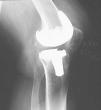

Realizamos una osteotomía del polo distal rotuliano, incluyendo superficie articular (fig. 5). Usamos el bisturí eléctrico para limpiar de restos óseos el tendón rotuliano. En los casos de artrofibrosis se produce un engrosamiento y metaplasia en el tendón rotuliano que hace que se pierdan los límites anatómicos normales de dicha estructura, apareciendo dicho tendón engrosado y englobado por una reacción fibrosa, por lo que realizamos la exéresis de tejido cicatricial, adelgazando el tendón mediante la extirpación longitudinal de las capas de fibrosis. De esta forma disminuimos la rigidez e incrementamos la longitud de dicho tendón, evitamos el posible roce del polo distal rotuliano con el labio anterior del polietileno y aumentamos el rango de flexión. Es el momento de evertir la rótula completamente; si no es posible se luxa lateralmente. Resecamos también la faceta lateral más marginal de la patela si es preciso, para evitar el roce de osteofitos con el cóndilo femoral. No realizamos la operación de Ficat si la rótula se encuentra centrada en las proyecciones de Merchant. Si flexionamos la rodilla aún más, accedemos a resecar todo el tejido periprotésico, LCP y cápsula posterior. Colocamos un implante de prueba sobre los dos tercios restantes de rótula. Una sobredimensión de 2-3 mm sobre el polo proximal rotuliano es aceptable, pero sólo fue necesario en nuestro primer caso, que resultó ser el más anquilosado. También se puede sobrepasar mínimamente el diámetro anteroposterior de la patela una vez protetizada con objeto de trasladar el tendón hacia delante, lejos del labio anterior del polietileno en flexión máxima (fig. 6). La convexidad de la rótula protetizada ayuda a impedir el roce del polietileno con el polo distal (fig. 7). La razón de no aceptar más de 2 mm de sobredimensión es que dudamos de la resistencia del hueso remanente en casos difíciles como estos4,9. Lo consideramos como límite de seguridad, teniendo en cuenta que hasta 5 mm no se ha relacionado con una mayor incidencia de fracturas de rótula, aflojamientos o pérdida de flexión3. Insertamos un nuevo polietileno del mismo grosor o inferior que el previo dependiendo de cada caso. En aquellos casos en que no había aflojamiento (tres primeros casos) se decidió no recambiar el componente femoral y elegimos un diseño de preservación del ligamento cruzado posterior con un LCP resecado. El principal motivo es evitar una cirugía agresiva que pueda conllevar más complicaciones10 de las necesarias. En el caso 3 se evitó colocar un polietileno ultracongruente debido a la gran prominencia de su labio anterior, específico de este diseño. En los casos 4 y 5 el recambio protésico era obligado por el aflojamiento previo. Esto permitió asociar otras opciones técnicas como la distalización de la interlínea.

Figura 5. Osteotomía del polo inferior de la rótula.